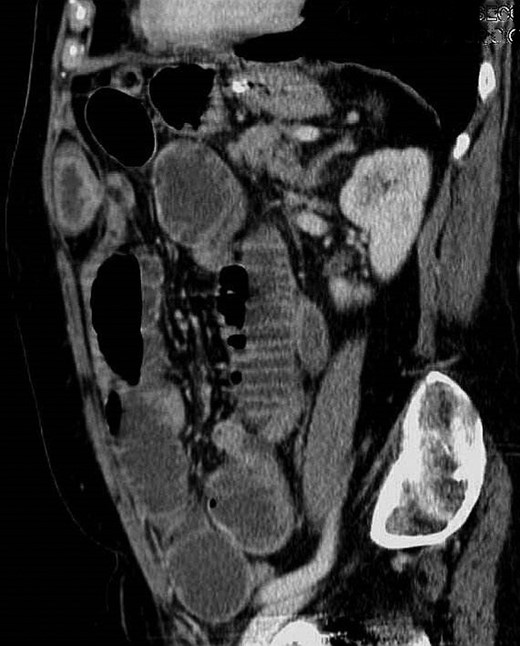

Blood tests were within normal limits except for an elevated serum creatinine of 1.3 mg/dl and C-reactive protein of 2.4 mg/dl. The abdominal X-rays showed small bowel distension with air fluid levels (Fig. 1). An abdominal computed tomography (CT) scan was performed diagnosing small bowel obstruction secondary to an incarcerated hernia in the left upper abdominal wall. The hernia defect lied through the internal oblique and transversus abdominis muscles aponeurosis with its sac extending posterior to the left rectus abdominis. There weren´t signs of intestinal ischemia (Figs 2 and 3).

CT scan—axial view of incarcerated hernia with its sac posterior to the left rectus abdominis.